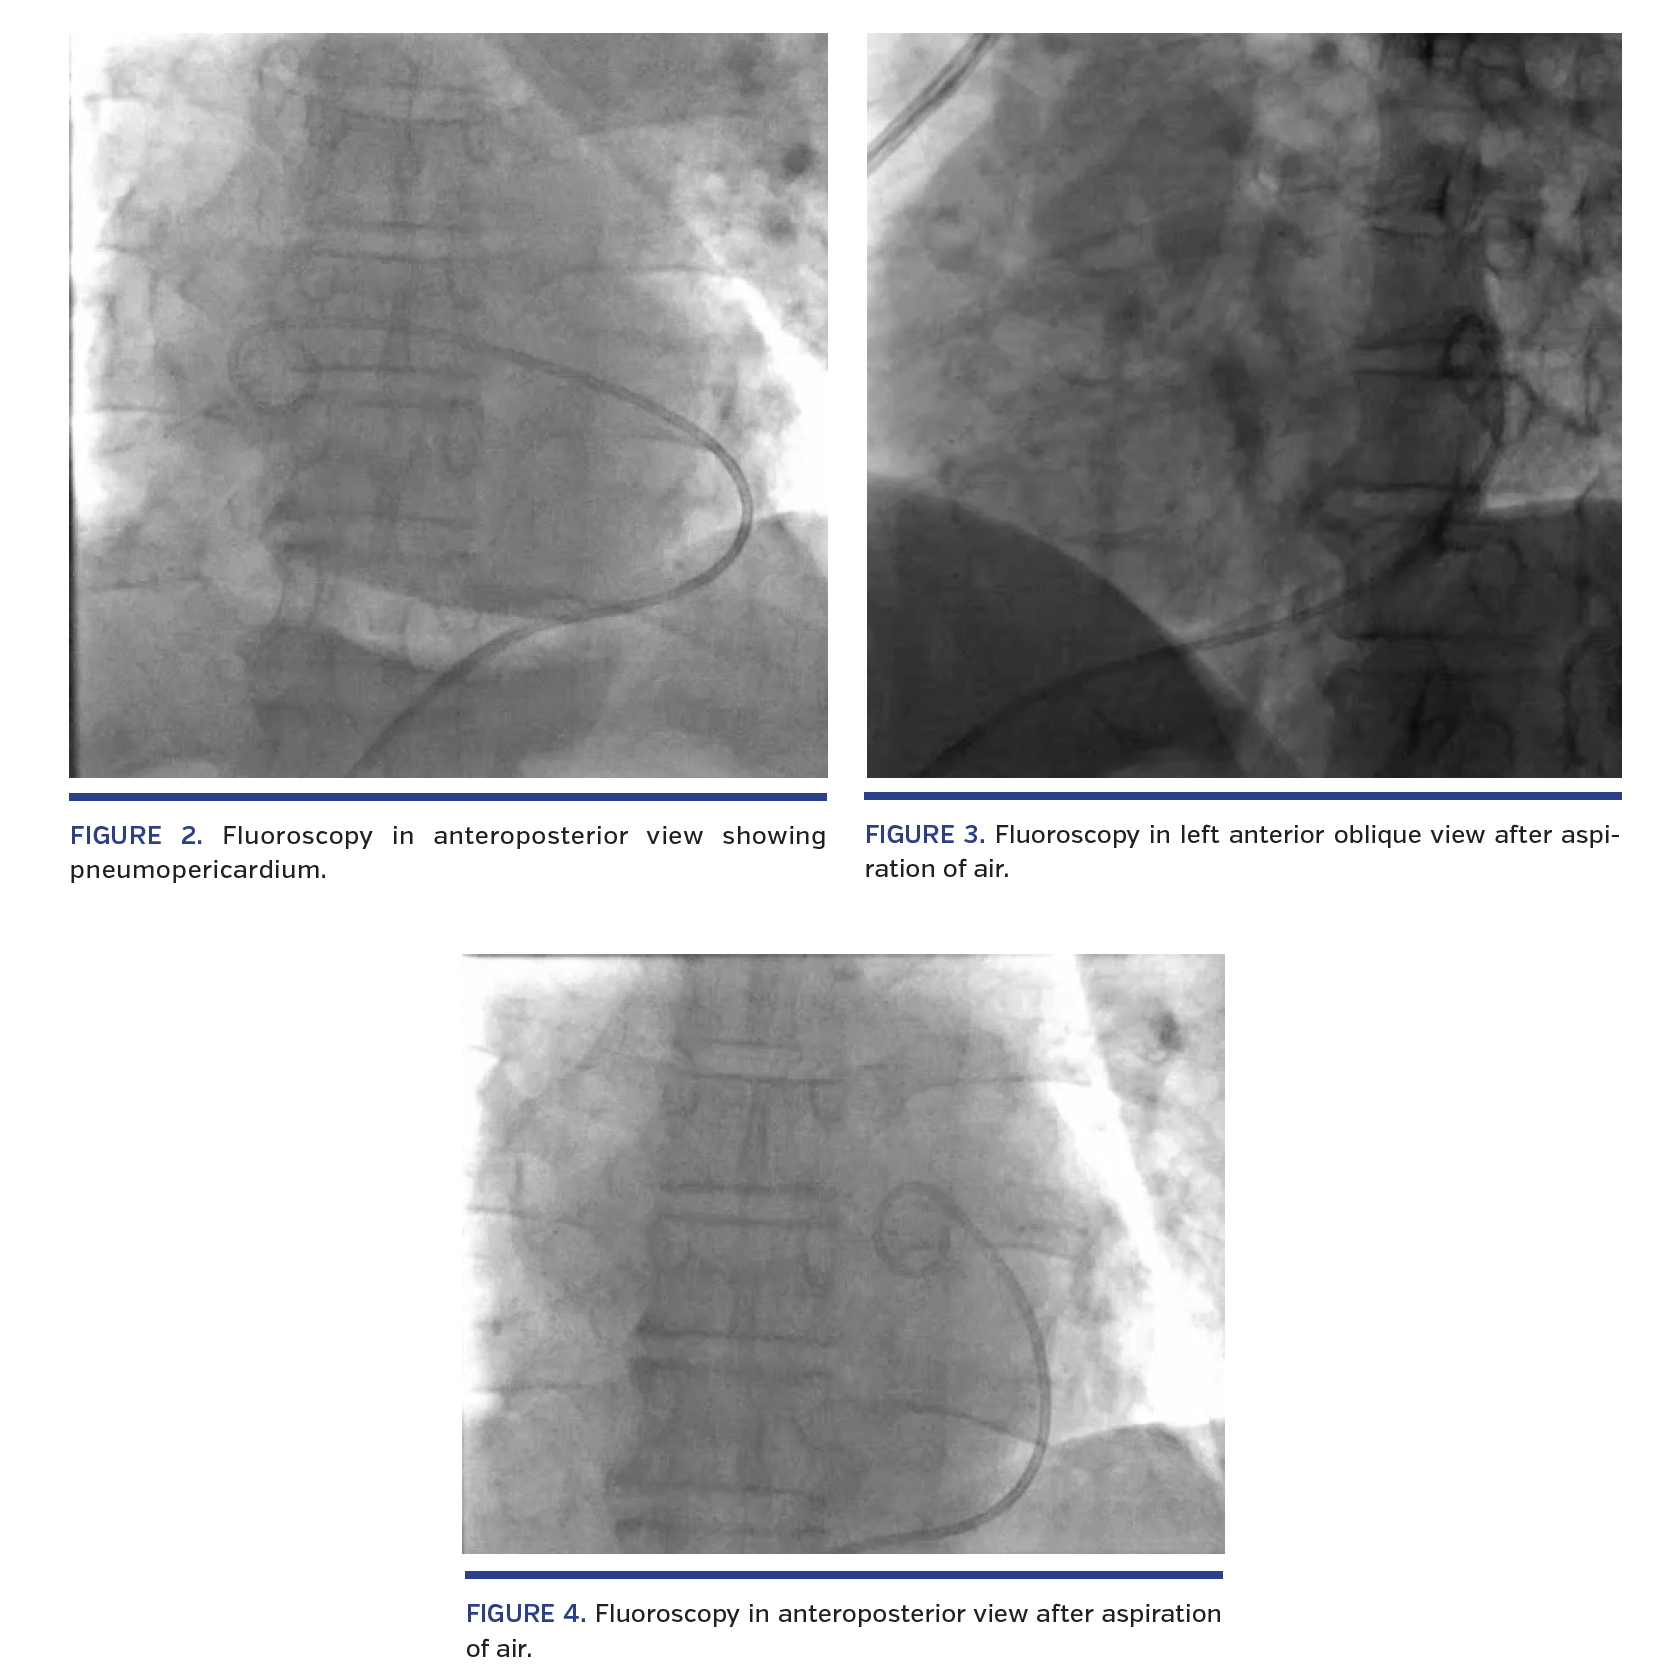

Emergent pericardiocentesis was performed by fluoroscopy-guided subxiphoidal approach. In the catheterization laboratory, a 7 Fr sheath was used to access the pericardial cavity using an over-the-wire technique. A 6 Fr pigtail was inserted through the 7 Fr sheath, following which 540 mL of blood were aspirated by pericardiocentesis. Concomitant blood transfusion was started. Blood pressure started improving and tachycardia settled. However, 5 minutes later, the patient again developed breathlessness with fall in systemic pressures. The transthoracic echocardiographic window became abruptly poor, with poor visualization of cardiac structures. Fluoroscopy was done immediately, which showed presence of air in the pericardial cavity (Figures 1 and 2; Videos 1 and 2). The side port of the 7 Fr sheath was accidentally opened and air was sucked into the pericardial cavity causing pneumopericardium and hemodynamic compromise. Closure of the side port followed by immediate aspiration of the air was performed (Figures 3 and 4; Videos 3 and 4). The patient became hemodynamically stable thereafter.